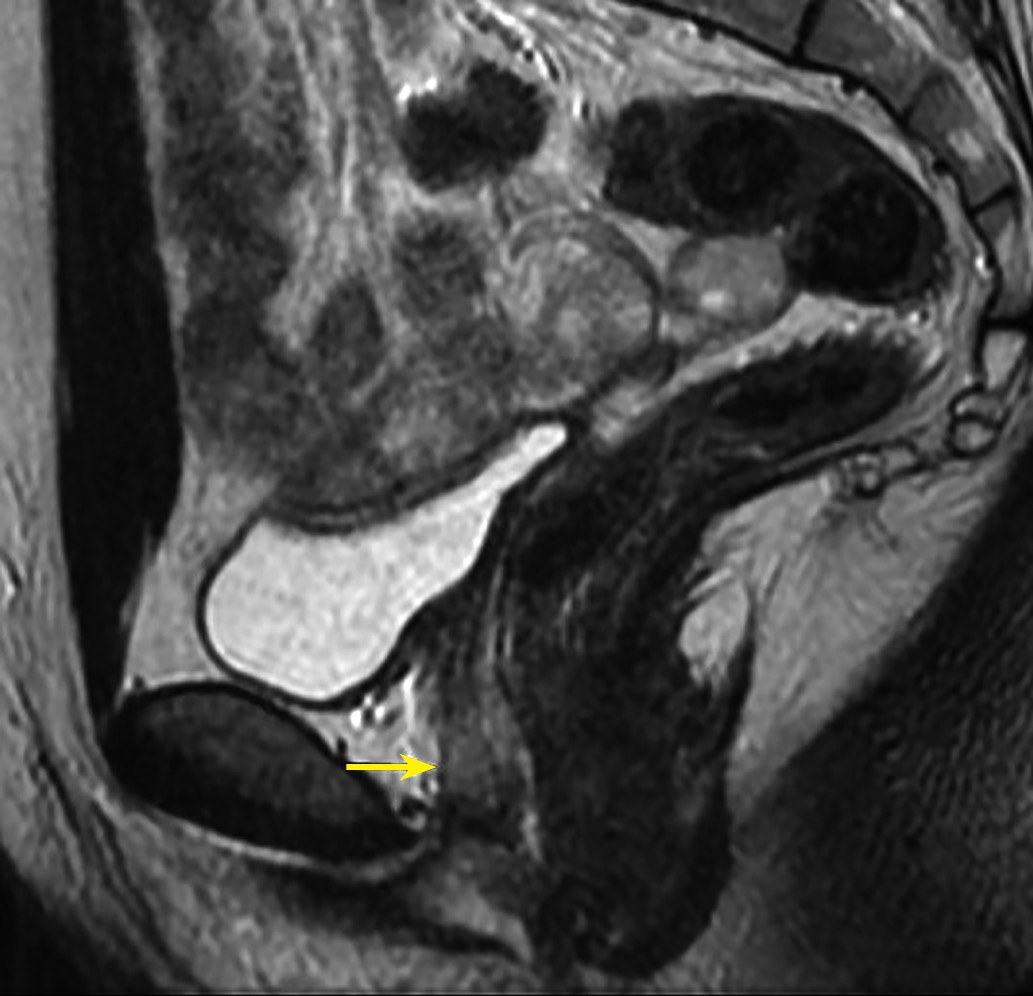

Рисунок 3 а, б. МРТ органов малого таза пациентки Х, Т2-ВИ, сагиттальная (а) и аксиальная (б) плоскости.

Примечание. Тубулярная структура ретровезикальной локализации, более вероятно соответствующая гипоплазии левого семенного пузырька. Справа семенной пузырек не визуализируется. Рис. а, б: кзади от мочевого пузыря, левее средней линии, определяется тубулярная структура с жидкостным содержимым, с неполными перегородками, максимальной толщиной стенки до 2,5 см, протяженностью до 5 см. МР-сигнал соответствует серозному содержимому с уровнем седиментации (стрелки).

Figure 3 a, b. MRI of the patient X pelvis, T2-WI, saggital (a) and axial (b) plane.

Note. The retrovesical formation of tubular structure is more likely to be the left seminal vesicle hypoplasia. The right seminal vesicle is not visible.Fig. a, b: a formation of tubular structure filled with fluid, with incomplete partitions, maximum wall thickness up to 2.5 cm and lenght up to 5 cm is defined posterior to the bladder, to the left of the midline. The MR signal corresponds to serous liquid with legible sedimentation level (arrows).